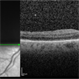

- macular fold, High Hyperopia

- Fundus Photograph of Left eye of a 17-year old Female Macular Folds with High Hypermetropia